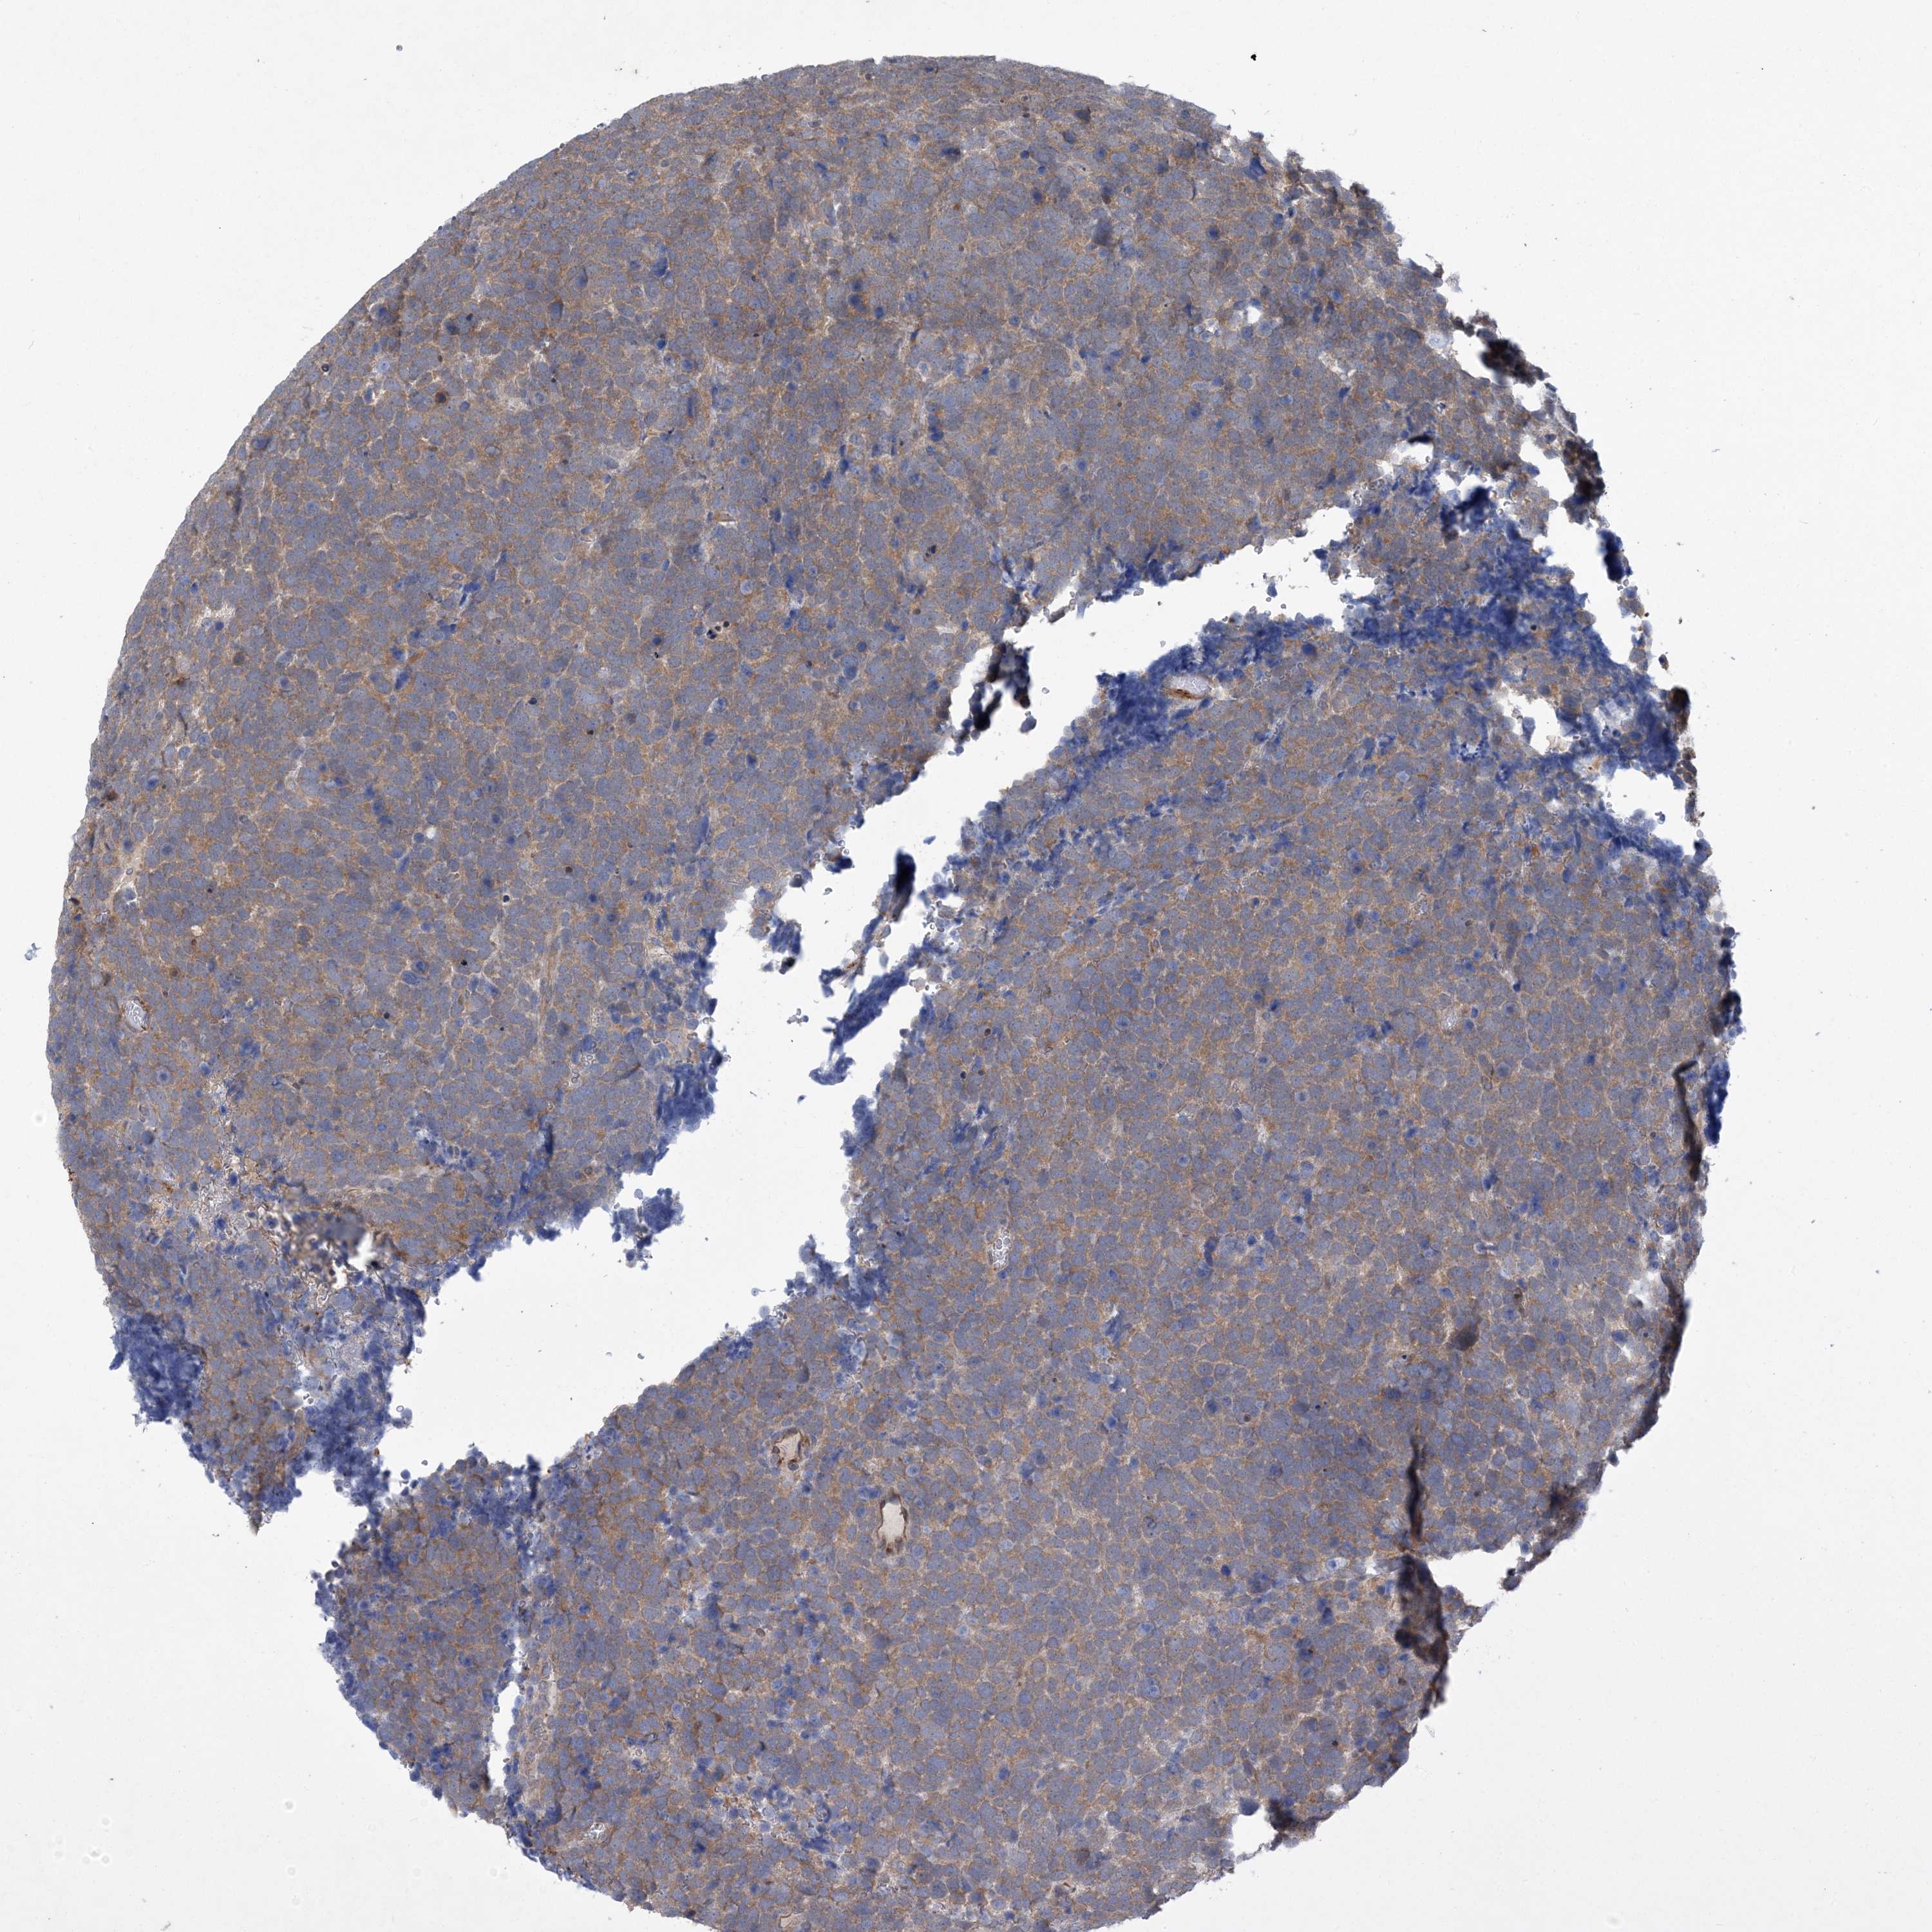

UROTHELIAL CANCER - Protein expressioni

A mouse-over function shows sample information and annotation data. Click on an image to view it in a full screen mode. Samples can be filtered based on level of antibody staining by selecting one or several of the following categories: high, medium, low and not detected. The assay and annotation is described here.

Note that samples used for immunohistochemistry by the Human Protein Atlas do not correspond to samples in the TCGA dataset.

Antibody stainingi

Antibody staining in the annotated cell types in the current human tissue is reported as not detected, low, medium, or high, based on conventional immunohistochemistry profiling in selected tissues. This score is based on the combination of the staining intensity and fraction of stained cells.

Each image is clickable and will lead to virtual microscopy that enables deeper exploration of all samples and also displays staining intensity scores, fraction scores and subcellular localization as well as patient and tissue information for each sample.

Antibody HPA035063

Antibody HPA035064

Urothelial carcinoma, High grade

Urothelial carcinoma, Low grade